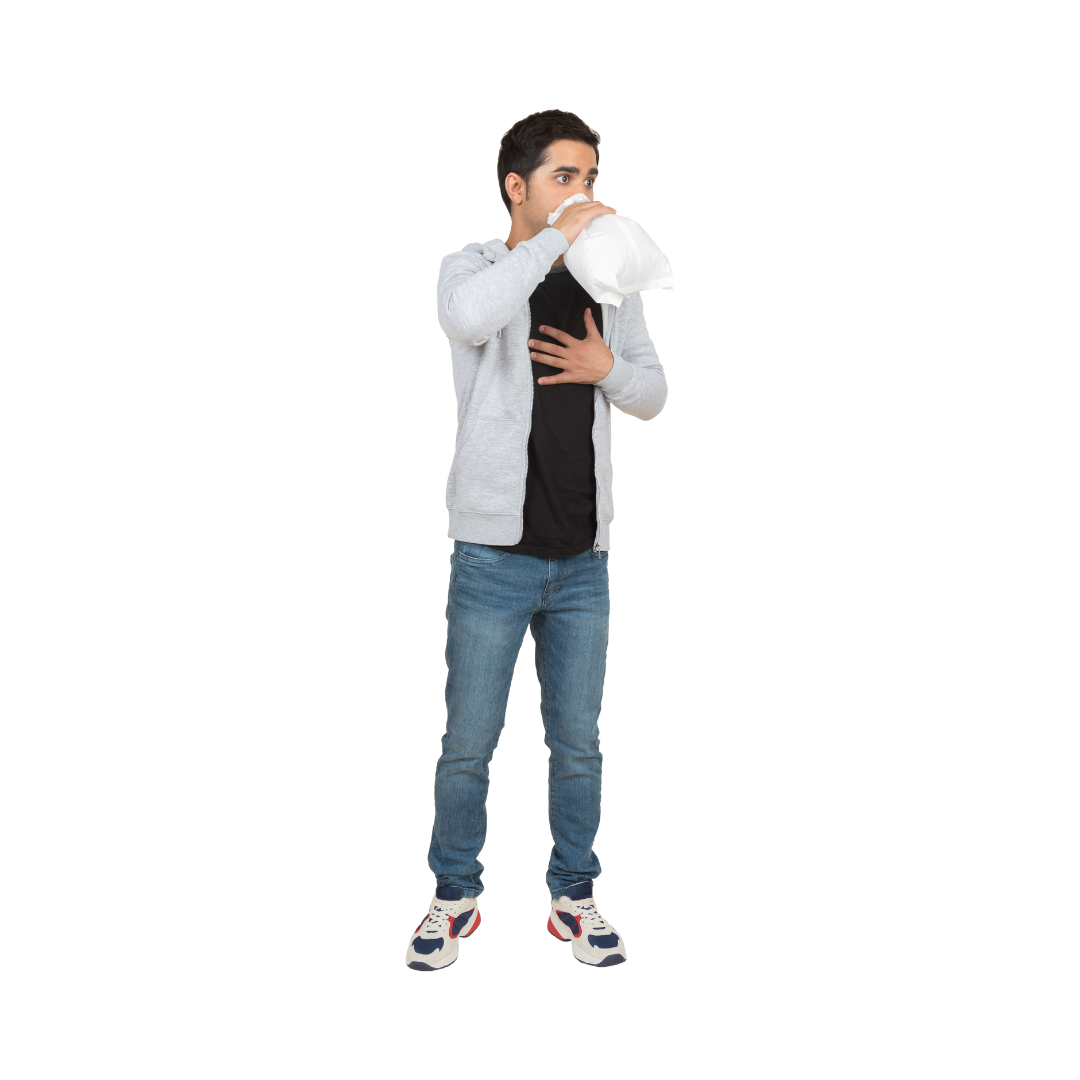

4. Laat het slachtoffer in zijn eigen handen ademen of gebruik hiervoor een zak.